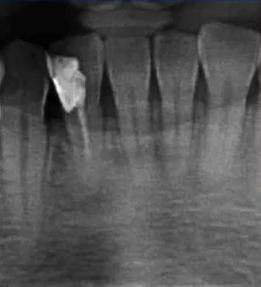

二次拍根尖片确认可看到根尖低密度炎症,临床检查与影像学检查相符,是根尖周炎。

曲面断层片怎么看口腔精读 | 一次性教你看懂曲面断层片!_https://www.jmylbn.com_新闻资讯_第21张

临床检查时发现14残根,牙龈红肿。曲面断层片上由于前磨牙转角问题,看不到残根,无法明确到底有没有残根,无法通过曲面断层片进行确诊或评估。

曲面断层片怎么看口腔精读 | 一次性教你看懂曲面断层片!_https://www.jmylbn.com_新闻资讯_第22张

这时需要加拍根尖片,很明显能看到残根。这就说明,有曲面断层片也不能排除情况。

临床检查45叩诊(+),牙颌面见畸形中央尖。加拍根尖片可看到,右下5根方有低密度影,并且右下5的牙根较短小,和曲面断层片上显示的大小不同,所以右下5是舌向倾斜的牙齿。